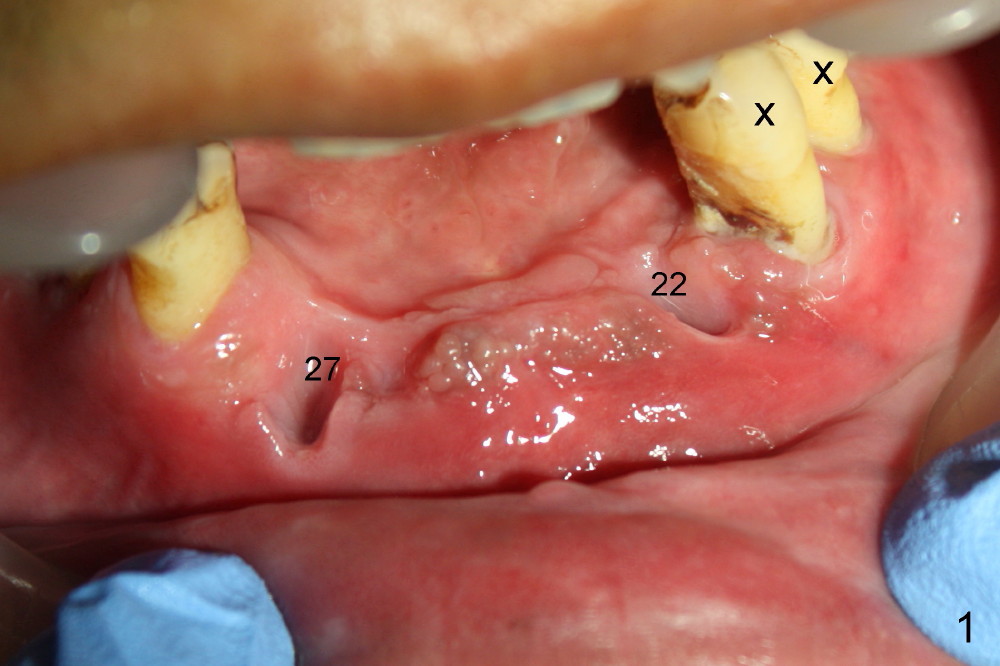

Treatment plan of the 1st surgery consists of extraction of #20 and 21/immediate implants (Fig.1 x), and placement of 4 implants between #22 and 27. Osteotomy at the extraction sites without incision (close surgery) turns out to be difficult; it appears to encroach the inferior alveolar nerve and mental loop. The sockets are subsequently bone grafted (Fig.2 *: mixture of autogenous bone and allograft). Incision is the made in the incisor edentulous region for placement of 3.5x17 mm implants (Fig.3 I).

Osteotomy is initiated through the gingiva of the healing sockets at the sites of #22 and 27 (Fig.1) with difficulty (close surgery). The incisor crest incision is extended distal to the canine areas; an accessory oblique incision is supplemented to facilitate implantation (#22: 5x14 mm; #27: 4.5x17 mm) and expose the buccal defects (Fig.3,4, open surgery). The defects are grafted (Fig.5) and covered by collagen membrane (Fig.6). The incisions are closed and abutments are placed for immediate provisional (Fig.7).